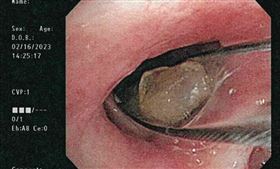

假牙少一顆竟卡在支氣管!嚴重恐釀肺塌陷

一名70歲患有巴金森氏症且長期臥床的李伯伯,因肺炎於...

2023/07/03 15:10